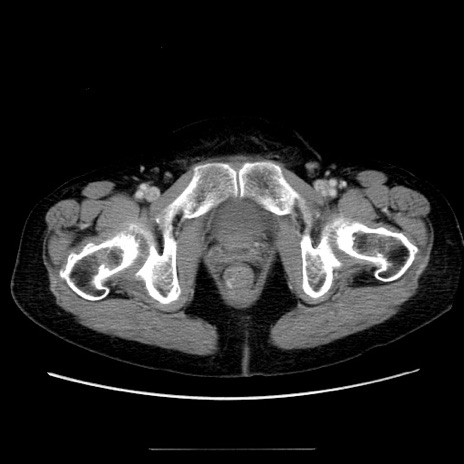

症例5(横断像)

【症例】70歳代女性

【主訴】お腹が張る

【現病歴】1週間くらい前から腹部膨満の自覚あり。昨日夜から増悪したため、本日救急外来受診。

【身体所見】意識清明、BT 36.5℃、BP 165/106mmHg、HR 80bpm、SpO2 98%、腹部:膨満、軟、自発痛・圧痛なし、触診にて不快感あり、腸蠕動音:減弱

【データ】WBC 12600、CRP 1.04